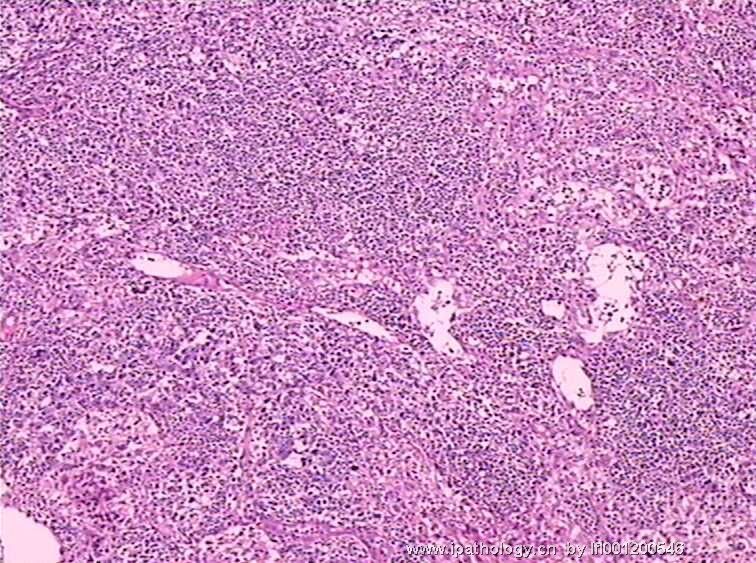

女,45岁,发现颈部多个淋巴结肿大,体查时发现全血细胞减少.取最大的淋巴结送检.

淋巴结结构破坏,有明显异常细胞,结合病史,考虑恶性,淋巴瘤、白血病?不知血片分类怎样?待组化和专家讲解。谢谢!

恶性,考虑淋巴造血系统肿瘤。NHL或白血病。

恶性是肯定,就是要排除转移的恶黑。再考虑原发的非何杰金